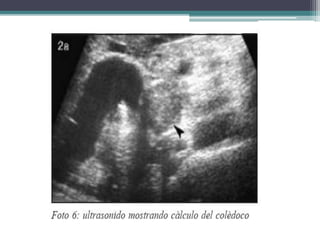

COLEDOCOLITIASIS

Migracion de un calculo

proveniuente de la vesicula

biliar hacia el coledoco

•Colico biliar

•Ictericia no acompañada de dolor

•Colangitis

•pancreatitis